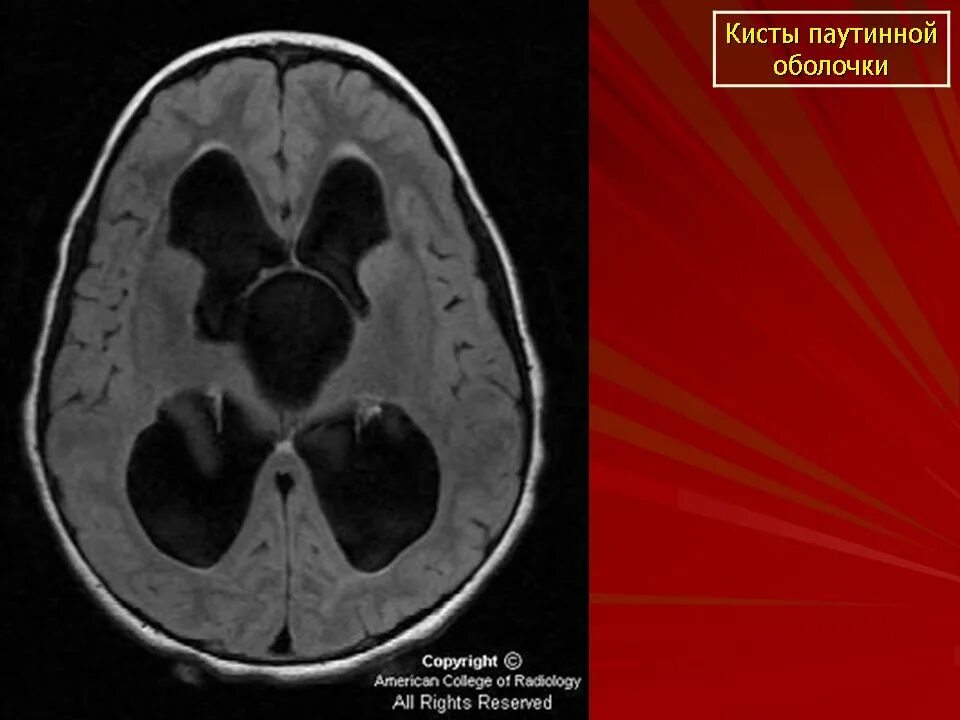

Ретроцеребеллярная ликворная киста